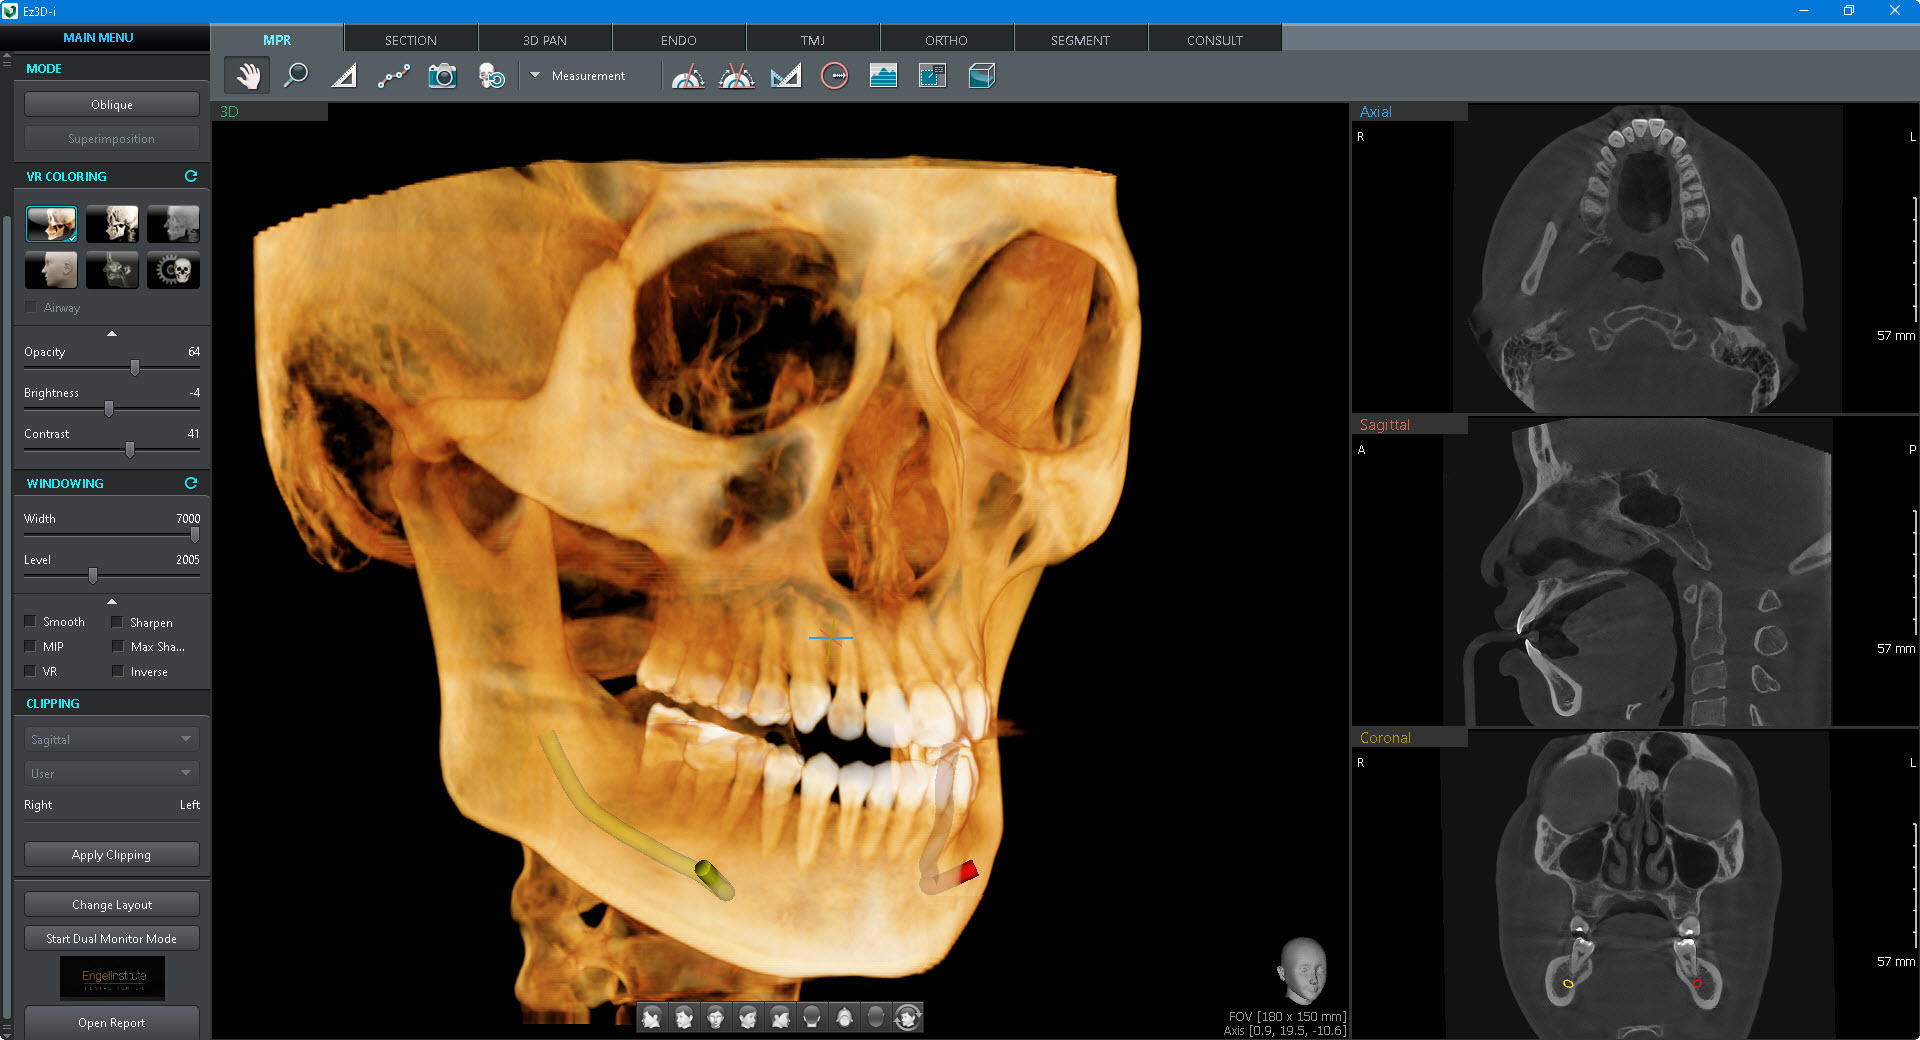

Tomógrafo 3D Dental con Ortopantomógrafo y Cefalostato.

- CBCT, Cone Beam Computer Tomography. Imágenes en 3D de 18 x 24 cm.

- FOV hasta 24 x 15 cm (Double Scan). Sensor 18 x 15 cm.

- Radiografía Panorámica (ortopantomografía).

- Radiografía Lateral de Cráneo (Ceph Rápido de 1. 9 Segundos).

- Radiografía de ATM.

- Radiografía de Senos Paranasales.

- Radiografía de Aleta de Mordida.

- Radiografía Carpal.

- Radiografía AP y PA.

- Radiografía Waters.

- Radiografía Submentovertebral.